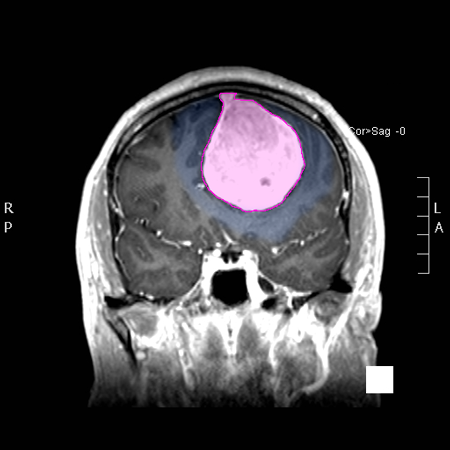

Περιγραφή Για την πραγματοποίηση της επέμβασης απαιτείται εκτενής προεγχειρητικός έλεγχος (καρδιολογικός, πνευμονολογικός και άλλος) και σχεδιασμός. Ως γενικό στόχο έχουμε την εξαίρεση του μεγαλύτερου δυνατού μέρους της εξεργασίας χωρίς να δημιουργηθούν μόνιμα νέα νευρολογικά ελλείμματα ή να επέλθει μόνιμη επιδείνωση παλαιοτέρων. Η ισορροπία ανάμεσα στον βαθμό εξαίρεσης και την πιθανή μετεγχειρητική νευρολογική έκβαση είναι μια ιδιαίτερα εξατομικευμένη απόφαση ασθενούς και ιατρού, ειδικά στους όγκους του παρεγχύματος του εγκεφάλου όπως τα γλοιώματα και αφορά όχι μόνο την περιεγχειρητική περίοδο αλλά και την εξέλιξη της νόσου στον χρόνοΗ επέμβαση δεν απαιτεί ξύρισμα του τριχωτού της κεφαλής πέραν 1 εκ. εκατέρωθεν της χειρουργικής τομής δεν είναι επώδυνη και ο χρόνος νοσηλείας είναι μερικές ημέρες (4-5), εκ των οποίων η πρώτη κατα κανόνα σε μονάδα εντατηκής θεραπείας ή αυξημένης φροντίδας, κυρίως για λόγους παρακολούθησης. Η κινητοποίηση του ασθενούς γίνεται το συντομότερο δυνατό και η ανεξαρτησία όσον αφορά βασικές καθημερινές δραστηριότητες (αυτόνομη σίτιση, προσωπική υγιεινή), επιτυγχάνεται στους προεγχειρητικά ικανούς πριν το εξιτήριο. Η επιστροφή σε πιο εκτεταμένη δραστηριότητα (εργασία, οδήγηση όταν επιτρέπεται) απαιτεί συνήθως μερικές εβδομάδες. |

Προϋπόθεση για τα ανωτέρω αποτελεί μια προεγχειρητικά καλή νευρολογική λειτουργία και μια ανεπίπλεκτη μετεγχειρητική πορεία. Ειδικοί περιορισμοί μπορεί επίσης να ισχύουν στους ασθενείς με επιληψία.